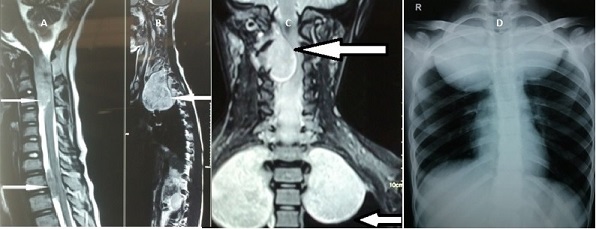

The MRI brain study revealed left vestibular and trigeminal nerve schwannomas and a posterior petrous meningioma on the right side [Table/Fig-1]. The spine MRI study showed intradural extramedullary lesions at C1-C2, C7, D1-D3 levels and multiple tiny lesions in the region of filum terminale [Table/Fig-2]. The dorsal lesions were seen extending to posterior mediastinum. The chest radiograph showed tumours occupying both the apices of the lungs, and on right side the lesion had extended to midzone as well [Table/Fig-2]. These findings lead to the diagnosis of NF2 [1].

MRI spine (A, B and C) showing intradural extramedullary lesions at C1-C3 and at D1-D3 levels and Posteroanterior Chest radiograph (D) showing tumours occupying both the apices of the lungs.